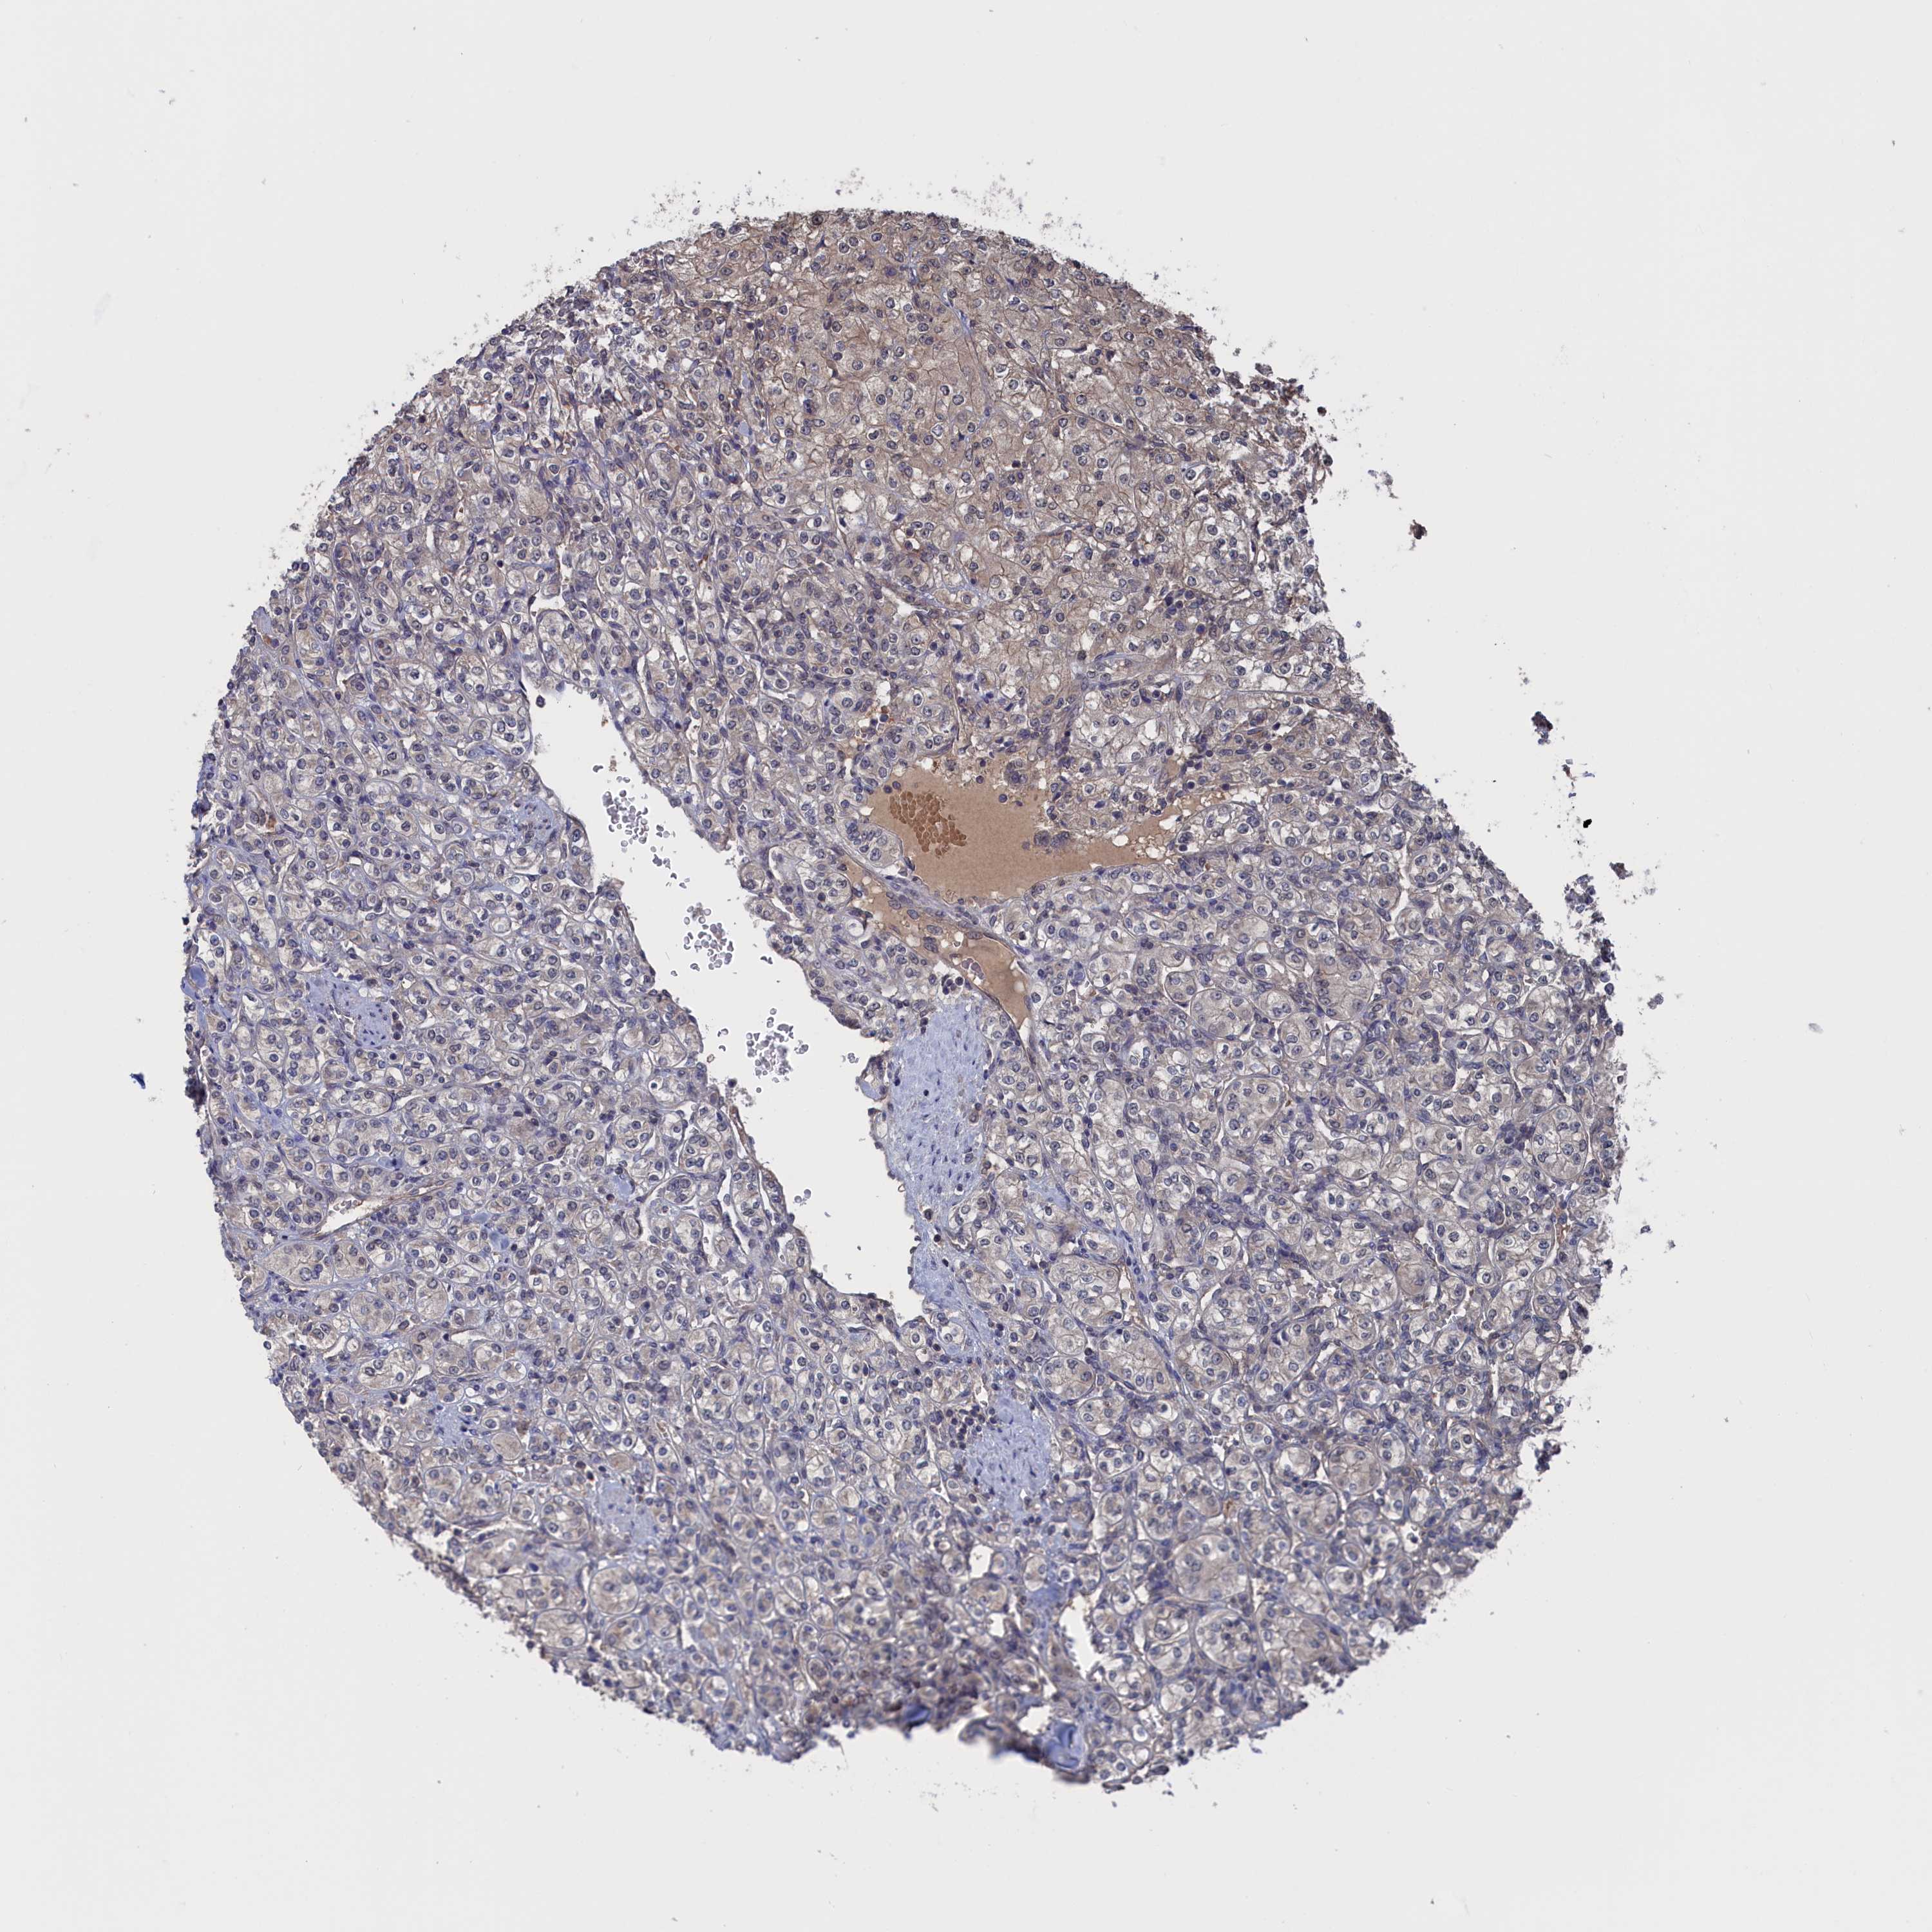

NUTF2 is validated prognostic, high expression is unfavorable in Kidney Renal Clear Cell Carcinoma (validation)

Best expression cut offi

Based on the FPKM value of each gene, patients were classified into two groups and association between prognosis (survival) and gene expression (FPKM) was examined. The best expression cut-off refers the FPKM value that yields maximal difference with regard to survival between the two groups at the lowest log-rank P-value. Best expression cut-off was selected based on survival analysis .

When clicking on this number, the vertical dashed line indicating cut-off, the interactive survival plot, and the Kaplan-Meier curve will be adjusted to show results based on the best expression cut-off.

: 76.52

Average pTPM 65.5

Number of samples 100